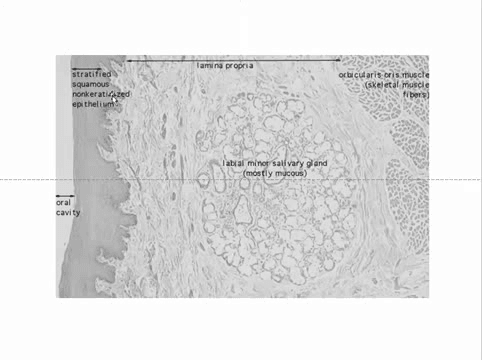

CAVIDAD-BUCAL.avi